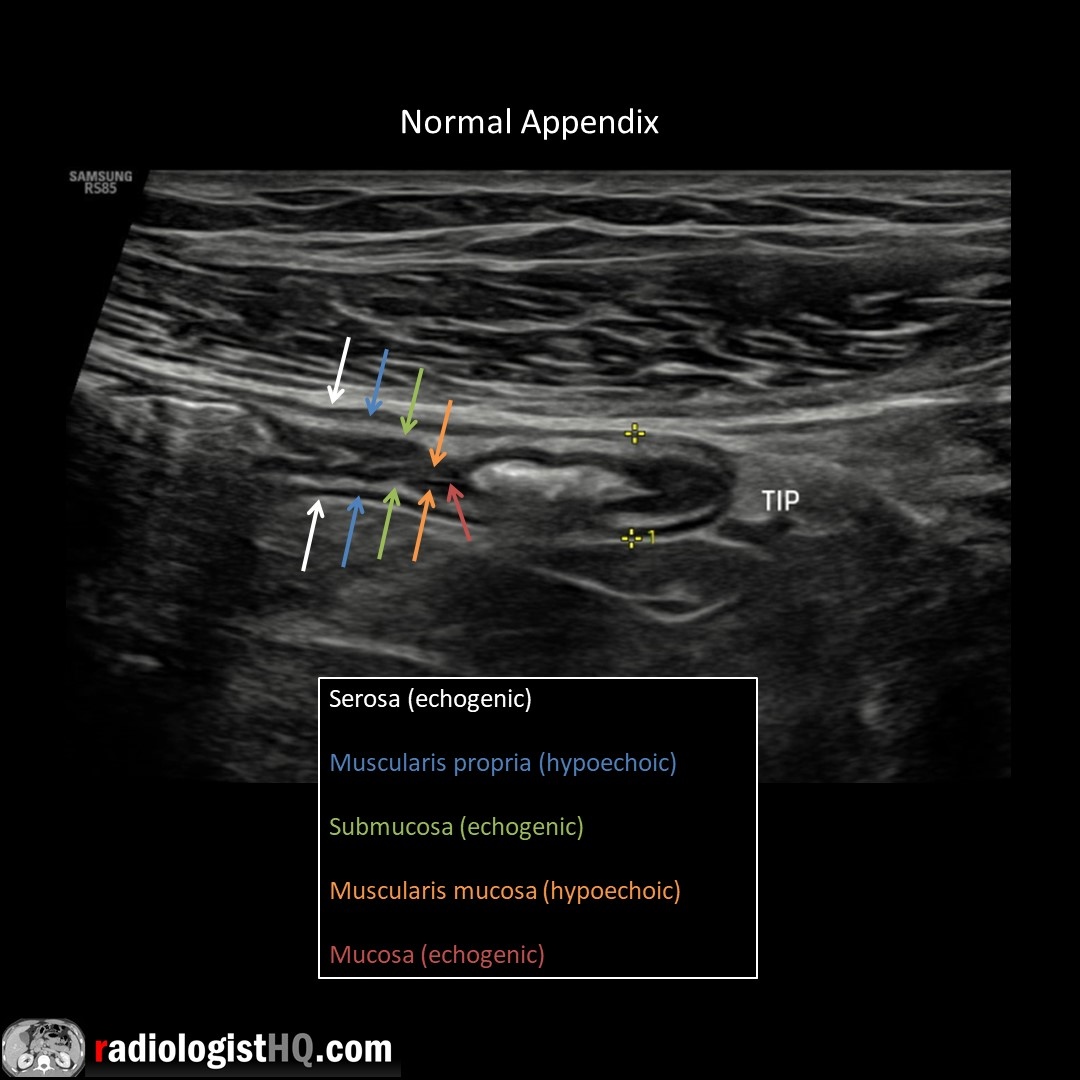

Normal, blind-ending appendix on US measuring 6 mm. Outer diameter <6 mm almost always normal, 6-8 mm borderline, >8 mm highly suspicious for appendicitis. Watch 📽️ video to learn more: bit.ly/rhq-appy Boston Imaging Samsung Healthcare #FOAMrad #FOAMed #radres #medstudent